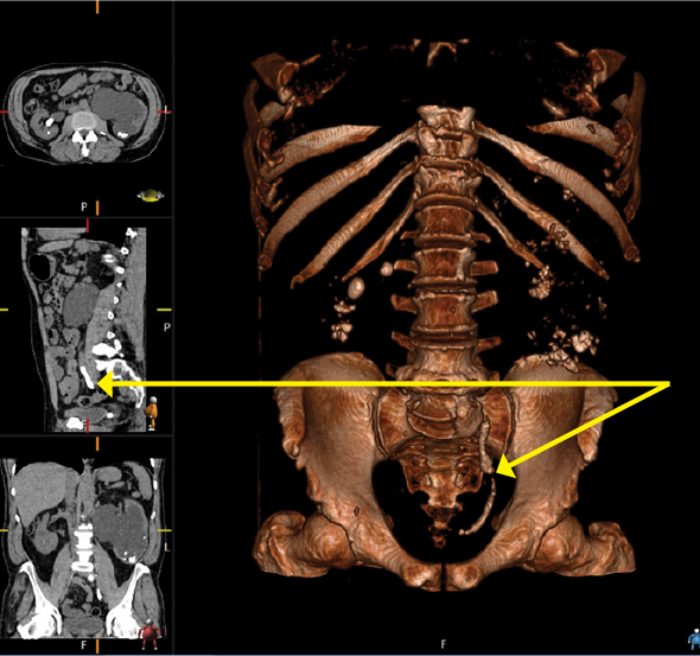

Case 4

A 57-year-old male presented with right flank pain. He had an established diagnosis of medullary sponge kidney and had been lost to follow-up. Serum creatinine was 114.

Figure 1: CT scout film demonstrating left ureteric stone on the opposite side to the patient’s pain.

Figure 2: 3D CT reconstruction demonstrating stone burden.

This is an example of a rarely seen ureteric stone burden.